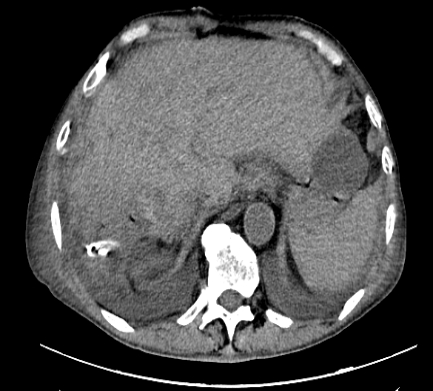

术后复查CT影像张建平主任介绍,肝胆管结石是一种常见的胆道疾病,其发病原因复杂,可以单独存在,也可以与肝外胆管结石并存。结石可诱发局部感染及继发胆管狭窄,感染及胆道狭窄促进结石形成,形成恶性循环,病情迁延不愈,严重者并发胆管化脓性感染、肝脓肿、急性胰腺炎,甚至诱发胆管癌,给患者的健康和生活质量带来严重影响。对于肝内胆管结石,只有早发现、早治疗、控制感染、去除病灶才是治疗之本。本例手术的成功,展现了济南市第五人民医院普外科团队在肝胆外科方面的综合诊治和应急处置综合能力达到省内先进水平。

面对困难,张建平主任带领团队凭借丰富的临床经验,果断决策,迅速制定了周密的手术与围手术期治疗方案,在积极控制感染、稳定内环境、做好充分呼吸道准备后,手术如期进行。术中探查发现,患者病情比影像学显示更为复杂:右半肝因长期结石梗阻和反复感染,已明显萎缩、纤维化,与膈肌等周围组织致密粘连,伴有膈下脓肿形成,稍有不慎分破膈肌将导致胸腔感染,术后肺功能衰竭。主刀张建平主任沉稳分离粘连组织,精细解剖肝门结构,牢牢控制每一支重要的血管与胆管。最终,病变的右半肝及胆囊被完整切除,胆总管内的结石也在胆道镜直视下被彻底取净,共取出结石数百枚,更有数枚直径可达2cm。手术过程流畅,出血仅约100余毫升。